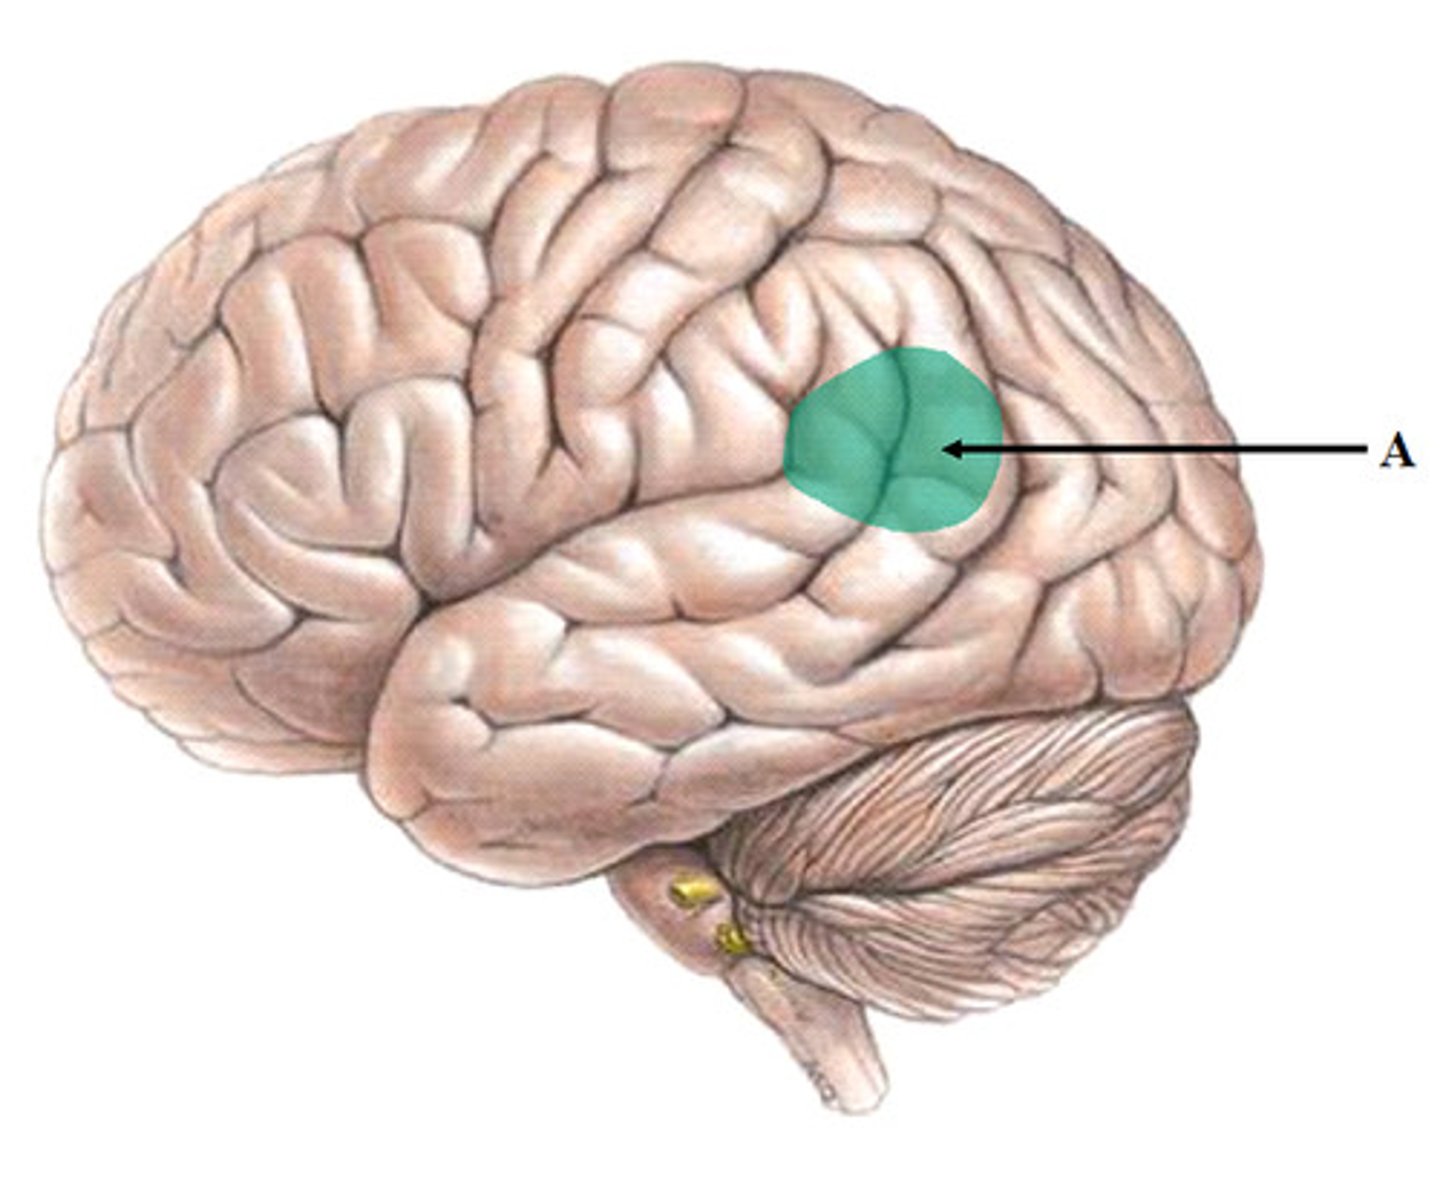

Wernicke's area

language center located in the left temporal lobe

involved in receptive language

if damaged, can lead to aphasia (inability to understand speech)

Wernicke is German and most people are not able to understand the German language